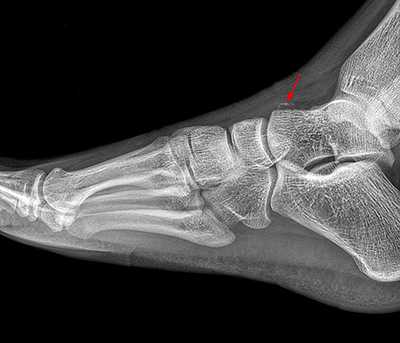

Рентгенологическое исследование

Для диагностики повреждения сустава Шопара делают рентген, КТ и МРТ. На передне-задней рентгенограмме определяют величину пяточно-кубовидного угла. Проводят одну касательную к наружному краю кубовидной кости и вторую касательную к наружному краю пяточной кости. В норме угол между касательными колеблется в пределах от 0 до 5°. Увеличение угла свидетельствует о нарушении стабильности пяточно-кубовидного сочленения. КТ во фронтальной и сагиттальной плоскостях позволяет выявить дефект суставных фасеток, смещение костей при вывихе и фрагментацию костей при переломе. КТ, по сравнению с рентгенографией, является более информативным методом диагностики. МРТ позволяет выявить дефекты отдельных связок.

Рис. 6. Отрывной перелом по тылу таранной кости на границе с суставом Шопара